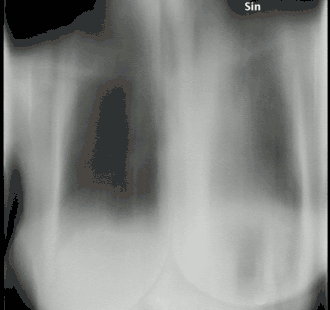

La tomosynthèse, ou tomosynthèse numérique, est une modalité d'imagerie médicale à haute résolution spatiale permettant de réaliser des tomographies à rayons X sur un angle limité, à des niveaux de dose similaires à la radiographie. Elle est particulièrement utilisée dans l'imagerie du sein mais elle a également été utilisée pour diverses applications cliniques, comme l'imagerie vasculaire, l'imagerie dentaire, l'imagerie orthopédique, l'imagerie musculo-squelettique, ou encore l'imagerie thoracique[1].

La tomosynthèse numérique combine l'acquisition et le traitement de l'image numérique, avec une chaîne d'acquisition radiologique classique tube/détecteur et une rotation de cette chaine par rapport à au sujet imagé, comme en tomodensitométrie (TDM). À la différence de la TDM, où l'ensemble source/détecteur effectue au moins une rotation de 180 degrés autour du sujet, la tomosynthèse n'acquiert de données que sur un angle de rotation limité (15 à 60 degrés). De plus, le nombre d'acquisitions réalisées le long de cet arc est inférieur au nombre de projections acquises en tomodensitométrie. Cette série incomplète de projections est numériquement traitée afin d'obtenir des images similaires à la tomographie conventionnelle avec une faible profondeur de champ. En raison du traitement de l'image numérique, une série de coupes d'épaisseurs différentes, à des profondeurs différentes peut être reconstruite à partir de la même acquisition. Étant donné que moins de projections sont nécessaires que la TDM pour effectuer la reconstruction, l'exposition aux rayonnements et les coûts sont réduits[4].

La résolution spatiale de la tomosynthèse (85 à 160 microns) permet de disposer de coupes plus fines qu'en tomodensitométrie, généralement de 1 mm à 1,5 mm. L'augmentation de la résolution des détecteurs permet une excellente résolution dans le plan de l'image, même si la résolution selon la profondeur des coupes est toujours moins importante. Le principal intérêt dans la tomosynthèse est l'imagerie du sein, comme une extension de la mammographie. Cette modalité offre un meilleur taux de détection avec un peu plus d'augmentation de l'exposition aux rayonnements ionisants[8],[9].